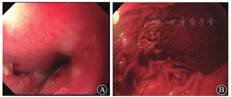

患者男,40岁,既往有糖尿病史,血糖控制不佳,否认肿瘤家族史,否认吞咽异物病史。此次因"消瘦10年,胸骨后疼痛、发热3 d"于2015年8月3日由急诊收治入院。临床表现为无明显诱因出现发热,体温最高达39 ℃,伴畏寒,无寒战,伴胸骨后疼痛,伴反酸、胃灼热、嗳气,且逐渐出现吞咽疼痛,遂入院治疗。入院体格检查:体温为37.4 ℃,脉搏为77次/min,呼吸为20次/min,血压为125/87 mmHg(1 mmHg=0.133 kPa);皮肤、巩膜无黄染,胸骨后无压痛,双肺呼吸音粗,未闻及干湿啰音,腹软,无压痛、反跳痛,双下肢不肿。入院诊断:2型糖尿病,反流性食管炎,咽炎,发热待查。给予抗炎、抑酸、保护胃黏膜治疗。入院后患者体温逐渐升高,出现呃逆,呕鲜血,胸骨后刀割样疼痛。实验室检查白细胞计数较前明显升高。8月5日行胸部CT平扫检查示:双侧胸膜增厚,双侧胸腔积液,食管旁憩室?食管扩张并管壁增厚。胃镜检查(图1)示:距门齿25 cm处食管3点位可见直径约0.5 cm的圆形孔道,较深,底部观察不清,胃腔内可见血液,考虑食管憩室、反流性食管炎、上消化道出血。给予加强抗炎、抑酸、止血、维持内环境稳定治疗。患者仍诉间断胸痛,8月6日复查胃镜(图2)过程中突发间断呕鲜血共约1 200 mL,出现低血压休克,迅速给予相关治疗维持生命体征。生命体征平稳后完善胸部CT增强检查(图3)示:主动脉弓局限性高密度灶,考虑主动脉假性动脉瘤可能?中上隔增宽,结构紊乱,多发积气,感染可能;食管中上段结构显示欠清,食管管壁不均匀增厚;纵隔内、左侧腋窝多发肿大淋巴结;胃腔内较多内容物;双下肺炎,双侧胸腔积液、心包积液。结合患者病史、影像学检查,考虑该患者可能为上消化道出血、主动脉瘘并出血、食管憩室炎、纵隔感染、类白血病反应、肺炎、胸腔积液、2型糖尿病。向家属说明病情建议行外科手术治疗。但患者突然出现血压下降,心肺复苏未成功,于8月6日18:00时临床死亡。